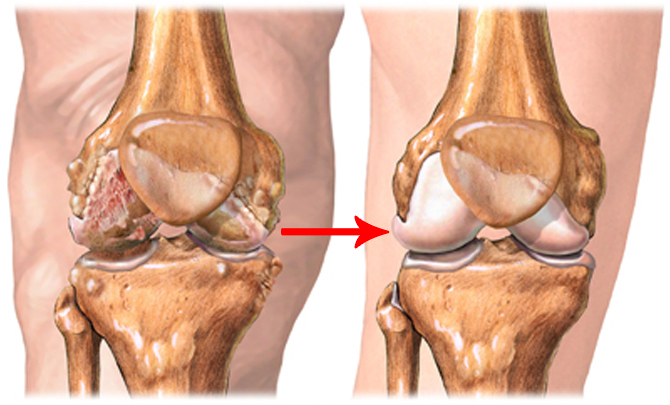

Julia comenzó a sentirse mejor cada día. Después de 7 días de tratamiento, fue al supermercado y compró algo de comida. En su rostro apareció esa sonrisa que tanto echaba de menos. 2 semanas más tarde, la artritis desapareció por completo. Parecía demasiado bueno para ser verdad, pero las pruebas mostraron que Julia estaba completamente sana, y yo estaba en el séptimo cielo. ¡Fue una verdadera victoria!

Gracias a su fórmula única, Motion Energy puede hacer frente a cualquier enfermedad articular:

- artritis

- artrosis

- coxartrosis

- osteoartrosis

- osteocondrosis

- osteocondritis

- osteoporosis

- lesiones de menisco

- gonartrosis